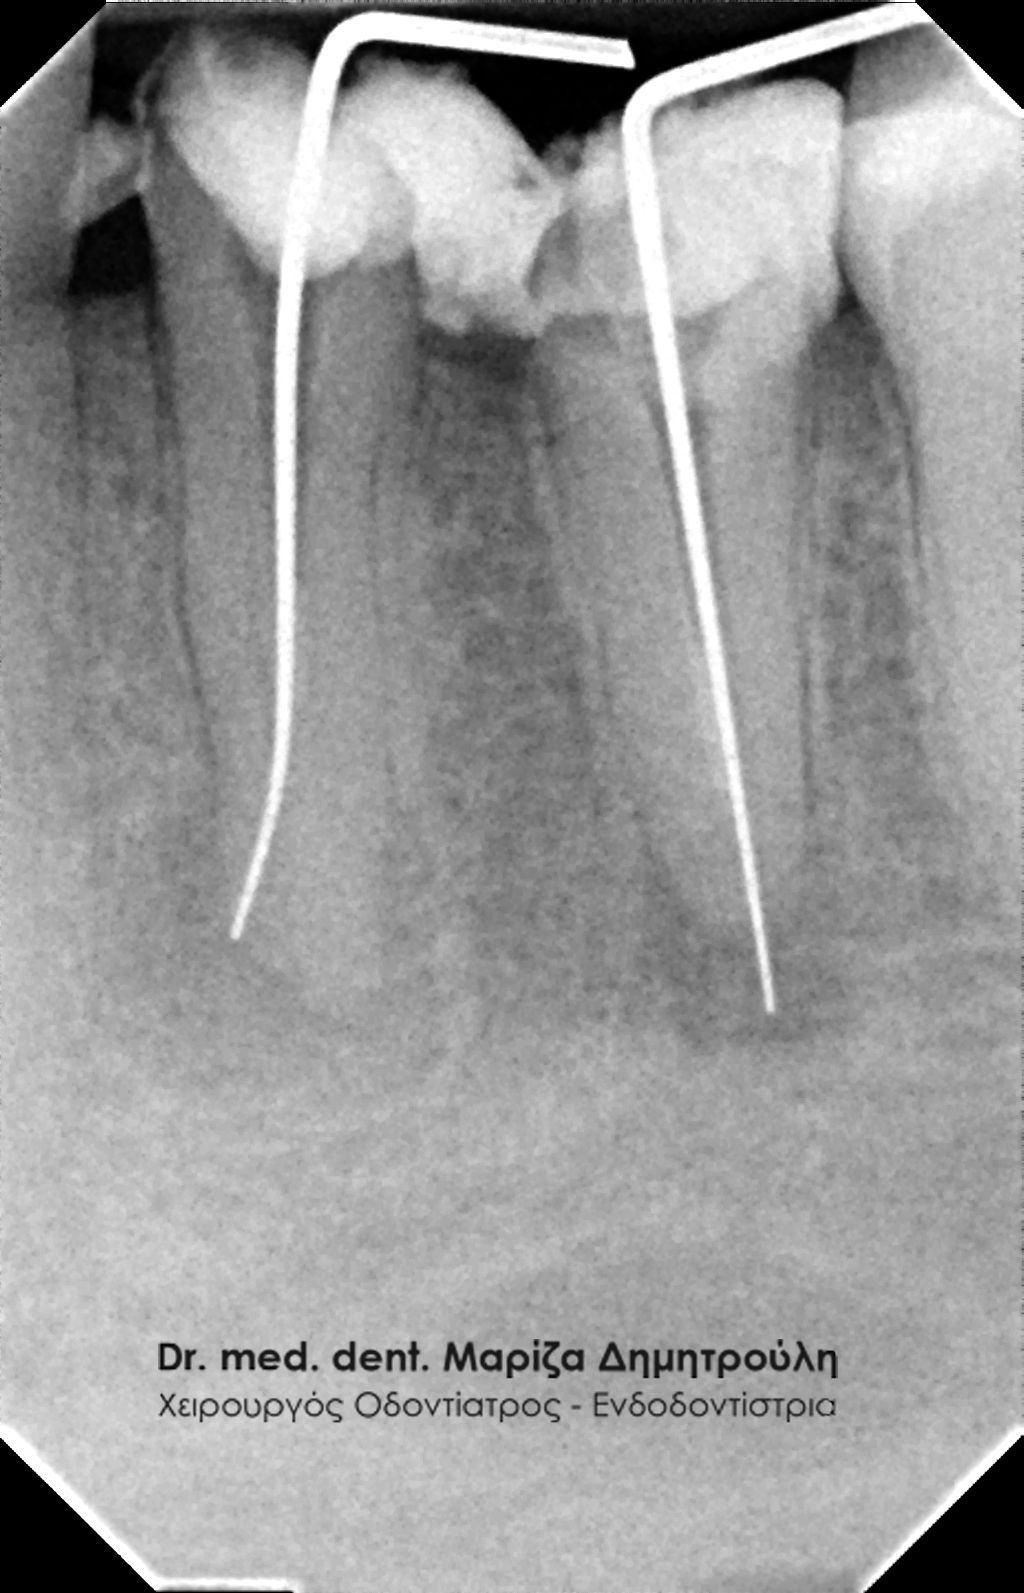

Περιστατικό – Απονεύρωση δοντιού με διάτρηση

Η ασθενής είχε ξεκινήσει μια ενδοδοντική θεραπεία (απονεύρωση) στον κάτω αριστερό πρώτο γομφίο πριν δύο εβδομάδες σε κάποιον άλλο συνάδελφο. Ανέφερε ότι από τότε ταλαιπωρείται με έντονο μόνιμο πόνο στο συγκεκριμένο δόντι. Της είχε χορηγηθεί αντιβίωση και παρόλα αυτά ο πόνος παραμένει.

Έγινε η κλινική και ακτινογραφικά εξέταση του δοντιού. Στην αρχική ακτινογραφία που πραγματοποιήθηκε πριν τη διάνοιξη του δοντιού παρατηρήθηκε ο έντονος εκτροχισμός του δοντιού ανάμεσα στις ρίζες. Η ακτινογραφική αυτή εικόνα γεννά υποψίες για πιθανή διάτρηση του δοντιού στο συγκεκριμένο σημείο. Διάτρηση ενός δοντιού κατά τη διάρκεια της απονεύρωσης μπορεί να προκληθεί όταν ο οδοντίατρος “ανοίγει” (τροχίζει) το δόντι στην προσπάθεια του να εντοπίσει τις ρίζες του δοντιού (ριζικοί σωλήνες). Είναι δηλαδή πιθανόν το δόντι να τροχιστεί σε άλλο σημείο από αυτό που εντοπίζονται οι ρίζες του δοντιού, με αποτέλεσμα να δημιουργηθεί μία τρύπα στο δόντι. Η τρύπα αυτή ονομάζεται διάτρηση.

Μετά από τη χορήγηση τοπικής αναισθησίας και την τοποθέτηση ελαστικού απομονωτήρα ακολούθησε η διάνοιξη του δοντιού. Αμέσως μετά την αφαίρεση του προσωρινού σφραγίσματος παρατηρήθηκε έντονη και απότομη αιμορραγία του δοντιού, η οποία προερχόταν από ένα συγκεκριμένο σημείο. Η κλινική αυτή εικόνα επιβεβαίωσε τις υποψίες για διάτρηση του δοντιού. Εντοπίστηκε το σημείο της διάτρησης και έγινε έλεγχος με μία ακτινογραφία. Στη συνέχεια πραγματοποιήθηκε η αποκατάσταση της διάτρησης με ειδικό υλικό και εντοπίστηκε ο τρίτος σωλήνας του δοντιού. Η όλη διαδικασία επιβεβαιώθηκε με τη λήψη ακτινογραφίας.

Αξίζει να σημειωθεί ότι η ασθενής μετά το πρώτο ραντεβού στο ιατρείο (στο οποίο βρέθηκε ο τρίτος ριζικός σωλήνας και “έκλεισε” το σημείο της διάτρησης) δεν πονούσε πλέον και το δόντι ήταν ασυμπτωματικό. Στην επόμενη συνεδρία το δόντι παρασκευάστηκε με ειδικά μηχανοκίνητα εργαλεία ενδοδοντίας και απολυμάνθηκε με ειδικά υγρά διακλυσμών. Η διαδικασία ολοκληρώθηκε με την έμφραξη των ριζικών σωλήνων (ριζών του δοντιού) με γουταπέρκα. Σε επόμενη επίσκεψη έγινε η αποκατάσταση του δοντιού με έμφραξη ρητίνης.

Επιβεβαίωση της διάτρησης

Εντοπισμός του τρίτου ριζικού σωλήνα